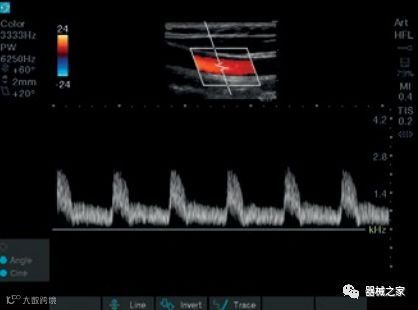

在几年前,超声波无法对小型慢流血管中的血流进行成像,但现在有少数供应商提供具有此功能的系统。该特征提供了另外一种检查病变以指示癌症或炎症的方法。其中一个是佳能Aplio 900 CV系统,它可以显示毛细血管中的血流量。日立的Arietta 65中程系统提供了一种可视化小血管的功能,可以更好地观察肾脏等器官的灌注情况。三星RS85还提供MV-Flow可视化慢流微血管结构。

采用芯片技术的超声系统允许通过简单的设置重新配置单个换能器,以将其成像为弯曲的,定相的或线性的探头,而不需要物理地具有和换出各种换能器。该系统还允许动态改变光束锐度,频率和焦深。该系统还提供扫描模式 - M模式,B模式和彩色多普勒。2-D蝶形传感器由9,000个元件组成,不使用传统的压电晶体技术。